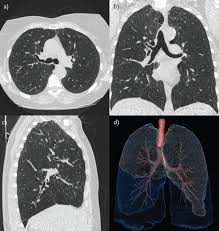

Cureus First Case Of Dendriform Pulmonary Ossification In Bahrain

Cureus First Case Of Dendriform Pulmonary Ossification In Bahrain from assets.cureus.com

Or a lump in a surgical patient. Interstitial lung disease seems to occur when an injury to your lungs triggers an abnormal healing response. No cartilage or rib excision had taken place in the previous operation. But in interstitial lung disease, the repair process goes awry and the tissue around the air sacs (alveoli) becomes scarred and thickened. Lung nodules are being recognized more frequently with the wider application of ct screening for lung cancer. Lung parenchyma, however, more extensively involves the bronchioles or lung airways, as well as key blood vessels located inside of the lungs. Parenchyma in the lungs essentially includes all systems and tissues pertinent to the lung's healthy functioning. We report the ct findings of parenchymal and pleural diseases in a group of patients with a history of asbestos exposure, excluding lung cancer (which is not typical in this subjects) and asbestosis (which is a parenchymal fibrosis). The closest locations of metastases of the primary lesions are in the peritoneum and bowels 7, 8. Each alveolus in the lung parenchyma opens directly into an alveolar duct or occasionally, in a limited number of species, into a respiratory bronchiole. Lung parenchyma is the substance of the lung that is involved with gas exchange and includes the pulmonary alveoli and respiratory bronchioles, though some authors include only the alveoli. Attention should be given to factors such as location, size, shape and density of an abnormality. Lung anatomy includes the lung parenchyma, which carries part of the conduction system but is mainly involved in the gas exchange at the alveolar level.

As the patient inspires, a curtain of grey air artifact sweeps from left (superior) to right (inferior) obliterating the view of the diaphragm and liver. Pneumonia is an infection of the lung parenchyma caused by a wide variety of organisms in pediatric patients. Parenchyma in the lungs essentially includes all systems and tissues pertinent to the lung's healthy functioning. Each alveolus in the lung parenchyma opens directly into an alveolar duct or occasionally, in a limited number of species, into a respiratory bronchiole. Or a lump in a surgical patient. Arises most commonly from pleura, with uncommon inward growth into lung parenchyma extremely rare to arise entirely within lung parenchyma generally peripheral in location pathophysiology. Lung parenchyma is the substance of the lung that is involved with gas exchange and includes the pulmonary alveoli and respiratory bronchioles, though some authors include only the alveoli. The percentage is higher on computed tomography which can detect disease when the radiograph is normal. If a large enough segment of parenchyma is involved, it can alter the transmission of air and sound. The most prominent structure in this region is the alveolus (figure 1). Pneumoperitoneum (or peritoneal emphysema) is air or gas in the abdominal cavity, and is most commonly caused by a perforated abdominal organ. Attention should be given to factors such as location, size, shape and density of an abnormality. If lung tissue is obtained, however, there is histologic disease in almost all patients, including those who have